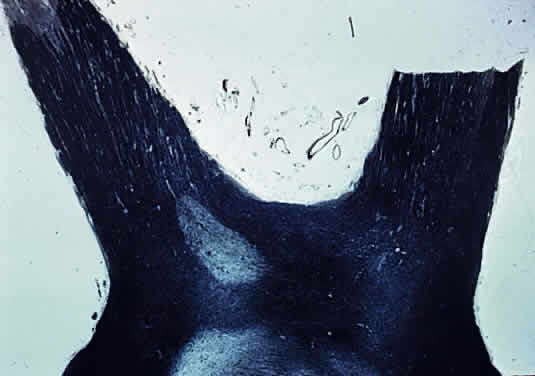

Fig. 2. Myelination of normal adult optic nerve up to lamina cribrosa (longitudinal section Luxol Fast Blue stain).